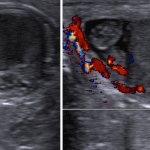

Indication: Right testicular pain

Torsed testicular appendage

Sample ReportRound, heterogeneous structure adjacent to the right epididymal head measuring 0.6 cm without internal vascularity, consistent with a torsed testicular appendage. Mild edema and hyperemia of the adjacent epididymis and small right hydrocele, likely reactive.

No evidence for testicular torsion.